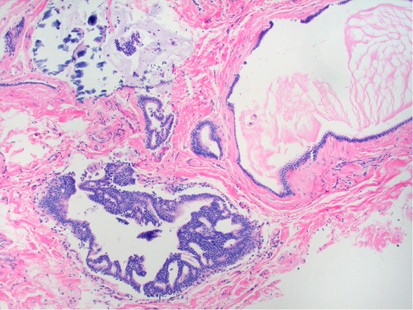

Using the pathology computer database of all core needle biopsy performed at our institution from 1 January 2000 to 1 June 2008, we identified 61/23 969 cases (0.25%) of benign mucocele-like lesions, all biopsied by radiologists. All specimens were received fixed and processed routinely. Of the 61 patients, 45 underwent surgical excision, whereas 5 refused surgery and have remained stable for over 1 year. Also, 11 patients were lost to follow-up. All core biopsies were reviewed to confirm the diagnosis of benign mucocele-like lesion defined by the presence of mucin-containing dilated ducts that ruptured, with resultant extravasation of mucin into surrounding stroma (Figure 1). All excision specimens were reviewed to confirm the final diagnosis and document biopsy site changes. Clinical, radiological, and pathological correlation was performed.

Benign mucocele-like lesion associated with calcifications diagnosed on core biopsy.